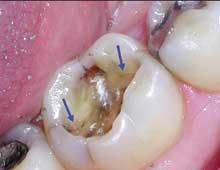

Under 3.5x or higher magnification, that peaceful row of gray-on-white may look more like a war zone. I use Class IV Orascoptic EyeMax loupes approximating a 5x view. This level of magnification took some getting used to, but now, little escapes me. In fact, I see things I never saw before. Where I previously saw old, but generally adequate alloy restorations, now I frequently discover minute coronal fractures subtly splitting a marginal ridge or areas of frank leakage that I previously missed (Figures 1 and 2). If you want to diagnose breakdown in progress, as opposed to waiting for inevitable failure, magnification is a must. It's one of several tools that give you more conviction when you make a diagnosis of pending failure. With more conviction comes greater confidence in your treatment plan. Your patients notice this and take your recommendations more seriously. Then, when you show them exactly why you believe their asymptomatic restoration is in jeopardy ... but now I'm jumping ahead of myself. Necessary as it is, magnification is just the first step.

Consider the mush and recurring decay you often find under unbonded amalgams, plus the fractures under weakened cusps or brazenly dead center in sub-amalgam tooth structures. (This is common in baby boomers when canine guidance has been lost.) When I remove an old, defective, amalgam restoration, I recall turning over a rock embedded in the earth and half looking away for fear of finding something scary. Use that simile when recommending replacement of old alloys. It will help you explain the situation (Figures 3 and 4).